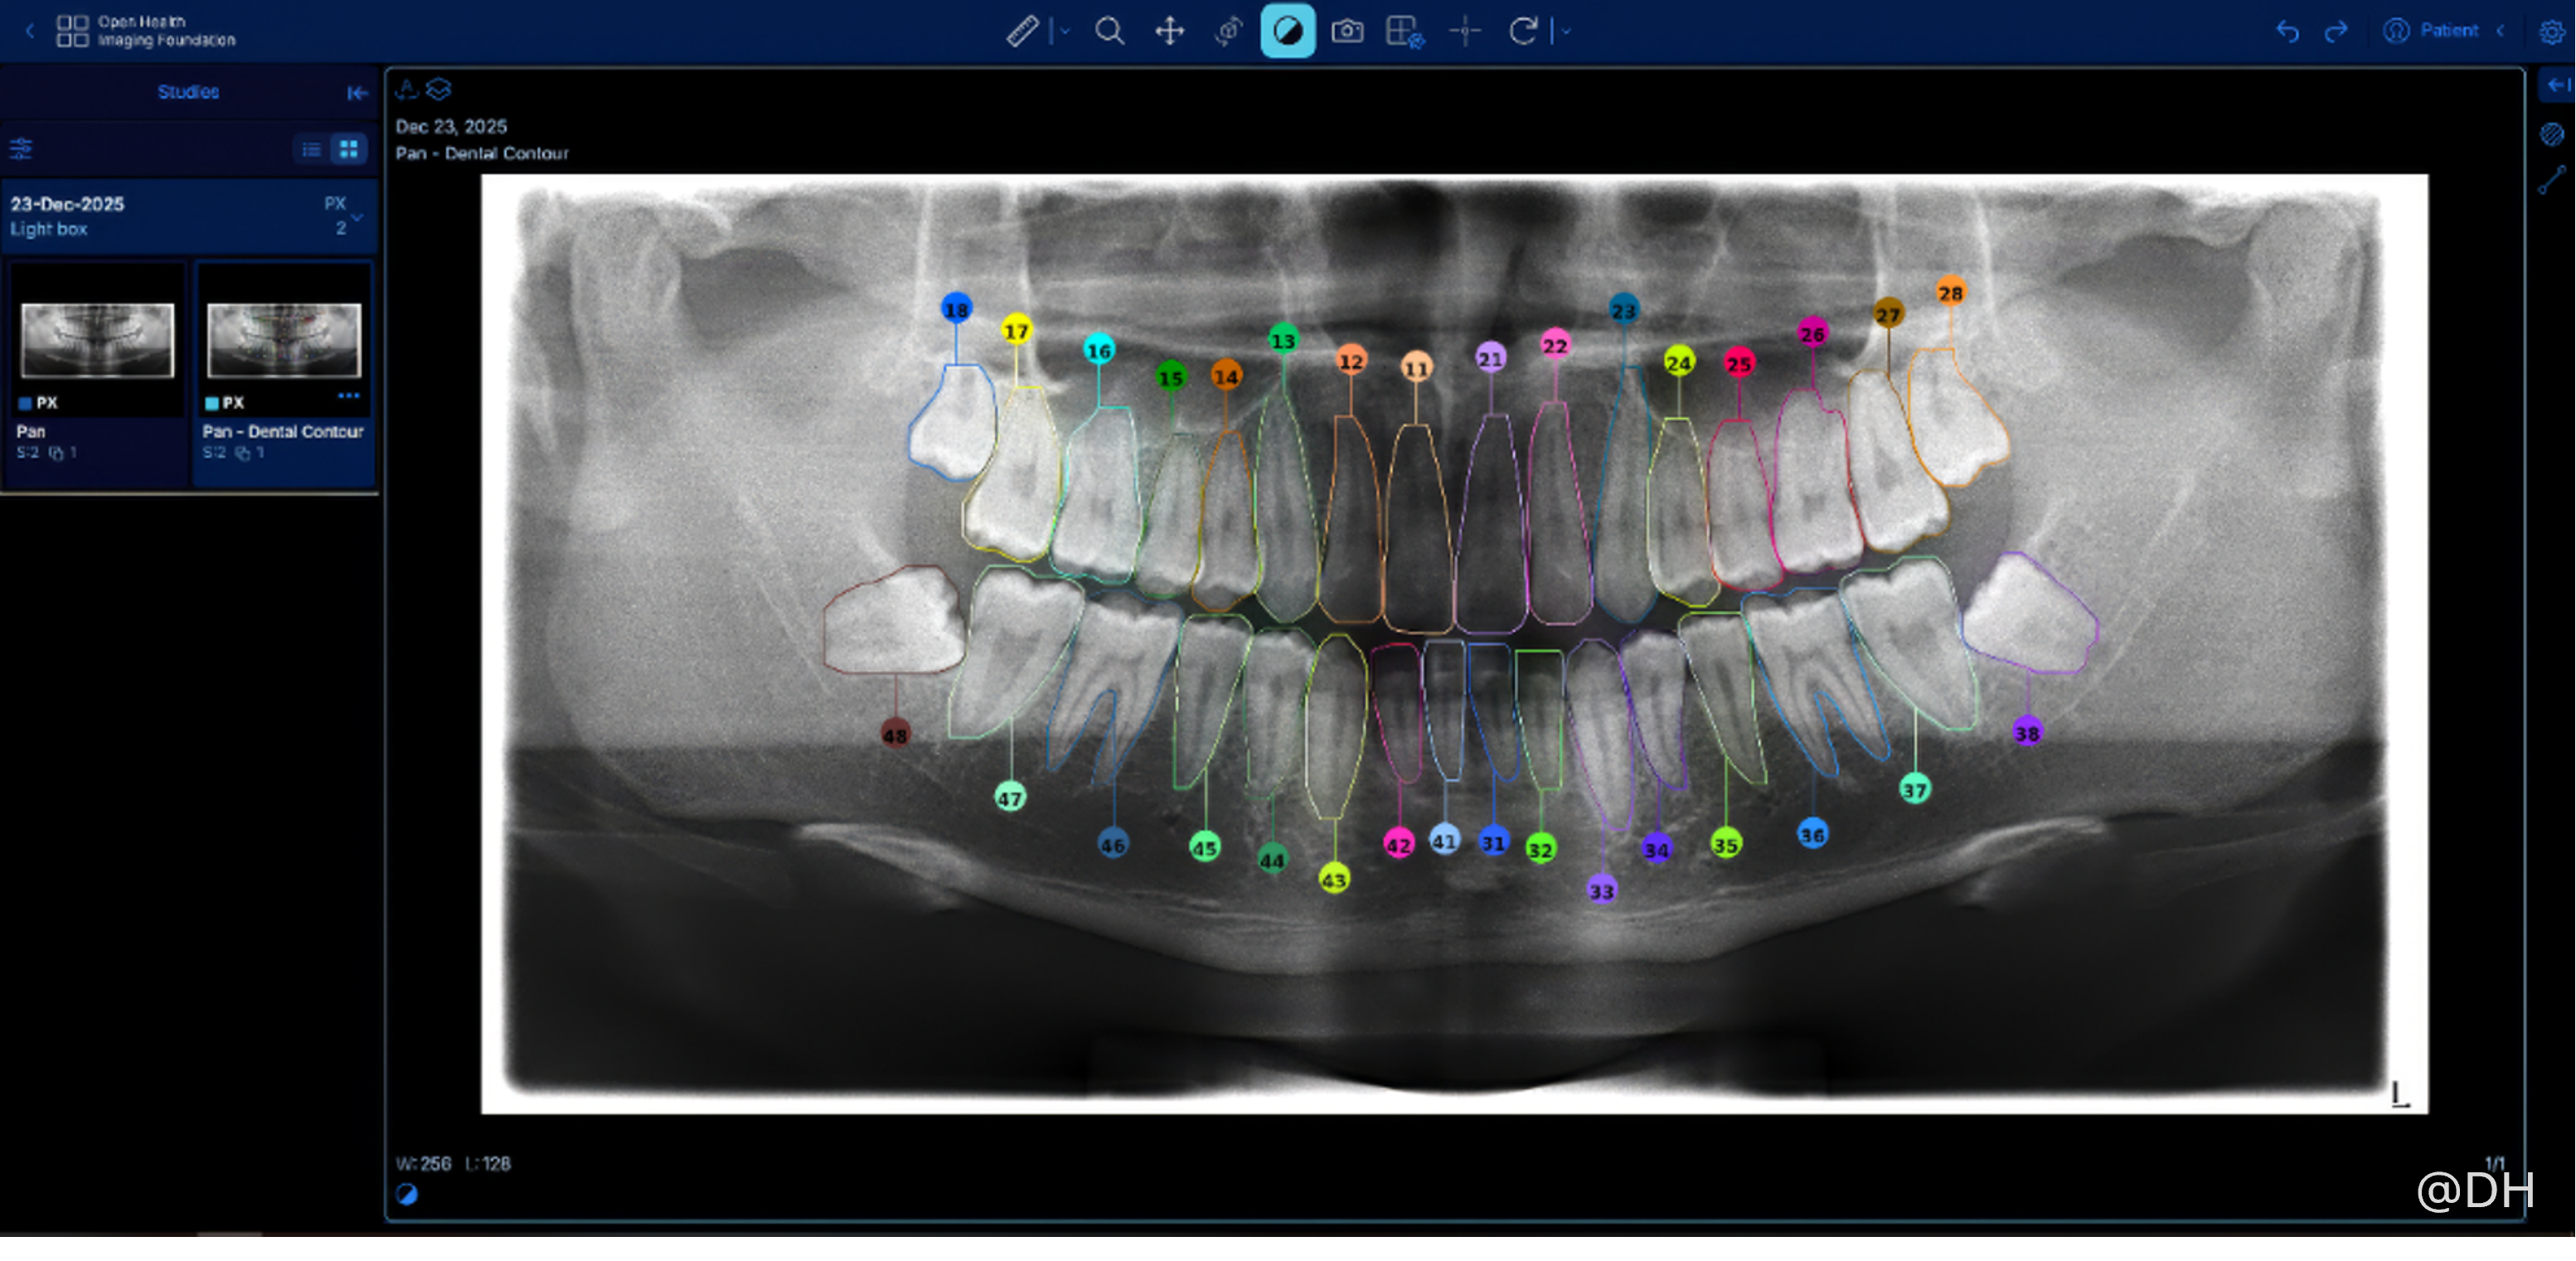

衞生署已採用電子臨床資訊管理系統多年,但工作流程上仍依靠人手輸入病人的臨床牙齒檢查資料,每個個案平均需時10分鐘。為減輕牙醫與助理的臨床文書負擔,優化服務流程,衞生署去年開展名為「人工智能輔助牙科圖表及解讀X光影像系統」的概念驗證項目。項目利用先進的半監督對比學習方法,以AI解讀牙科X光影像,AI先自動偵測並分割牙齒影像,根據空間與形態特徵為每夥牙齒標註國際牙科聯盟(FDI)牙齒編號;項目同時驗證了將影像分析轉化為結構化資料,自動生成牙科圖表,並與臨床管理系統整合的潛力。

為期約六個月的概念驗證項目已於今年一月成功完成,項目所發展出的解讀牙科X光影像的AI原型,臨床案例靈敏度高達96%,牙齒級精確度高達94%,效果令人滿意。